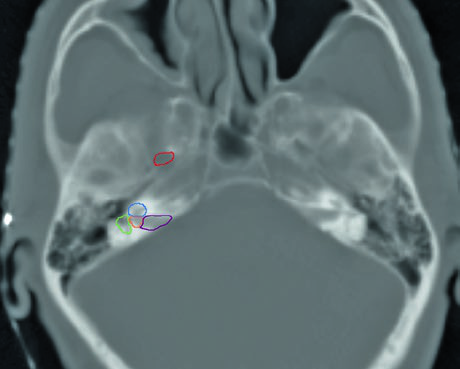

Skull base structure delineation must be performed using bone windows on CT. Key landmarks include: the foramen ovale (red), cochlea (blue), vestibule (orange), internal auditory canal (violet), and semicircular canals (green). Correctly identifying these structures is critical for ensuring adequate neural pathway coverage without excessive irradiation of sensitive structures such as the cochlea.

My recommendation is to contour these structures as organs at risk before expanding the CTV toward the skull base. This makes it possible to objectively evaluate dose-volume relationships and make conscious decisions about how much coverage is truly needed versus the cost in auditory or neural toxicity. A similar approach is used in nasal cavity and paranasal sinus delineation, where the skull base also plays a central role.